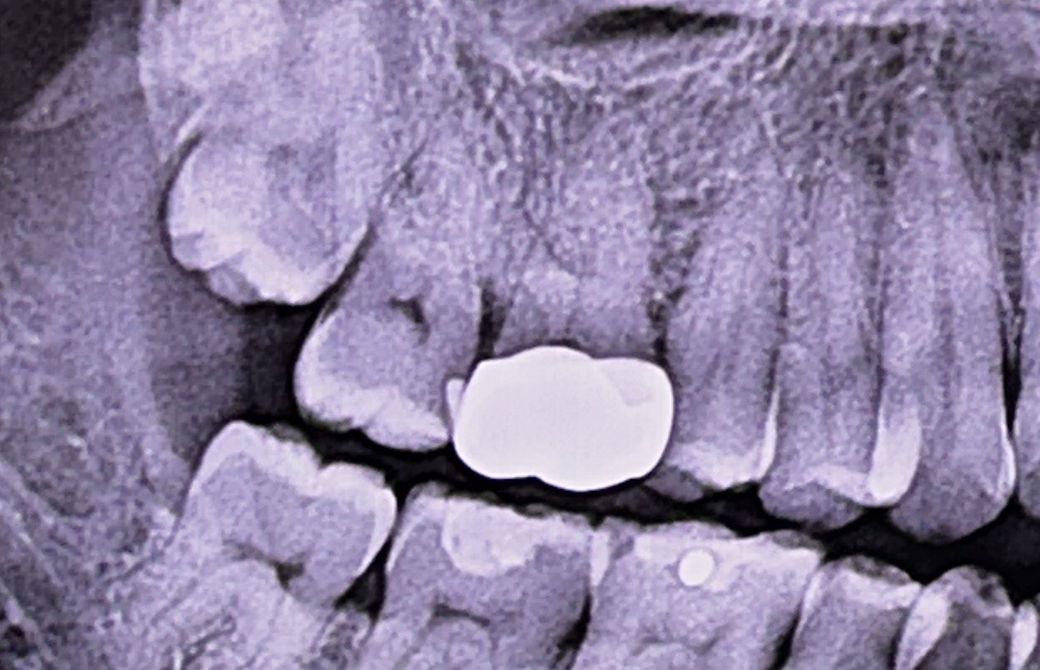

CT 사진 첨부해봅니다

CT상으로 볼쪽 뼈가 녹아보이기는 하지만 한 단면의 한 컷 만으로 확정짓기는 어렵습니다.

사랑니 발치가 크게 영향을 주었을 것 같진 않습니다. 다만, 첫번째 엑스레이 사진 상 크라운 하방 이차충치가 약간 의심되긴 합니다. 별개의 문제로 봐야할 것 같습니다.